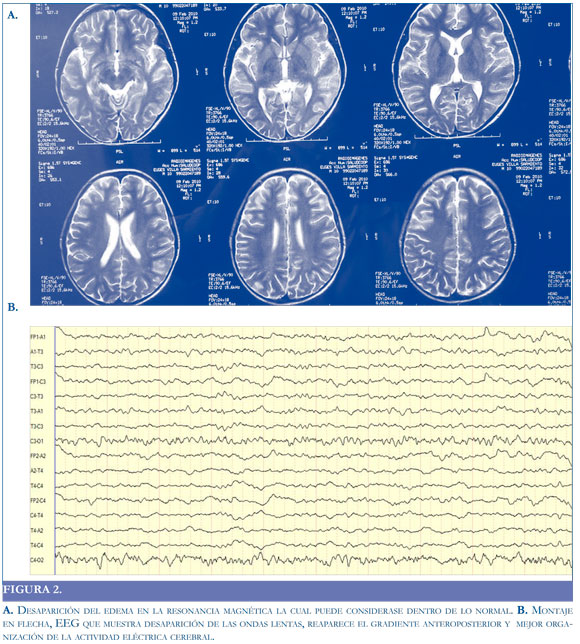

Por mejoría de los síntomas, se trasladó a sala de hospitalización, donde se inició manejo sintomático, se encontró mejoría de la fuerza en hemicuerpo izquierdo y no volvió a presentar episodios convulsivos. Se encontró desaparición del edema en la RM y el EEG mostró desaparicion de las ondas lentas y mejor organización de la actividad eléctrica cerebral (Figura 2).

Algunos autores sugieren que si el compromiso es cortical (sustancia gris), predomina la actividad delta polimorfa y si el compromiso es subcortical, los patrones arrítmicos son más comunes. Por lo general, la severidad del cuadro clínico se corresponde con las anormalidades registradas en el EEG (19). En el caso presentado, el EEG en la etapa aguda de la enfermedad mostró un ritmo de fondo delta, polimorfo, difuso (bilateral), no reactivo que se fue organizando en la medida en que el paciente fue mejorando clínicamente.

En este caso se evidencia la utilidad de ambos estudios en el diagnóstico y evolución clínica de la encefalopatía; debido a que su normalización se correlaciona con la mejoría de la sintomatología, sugerimos que estos estudios (Resonancia Magnética y electroencefalograma) deben practicarse en forma seriada a este tipo de pacientes.